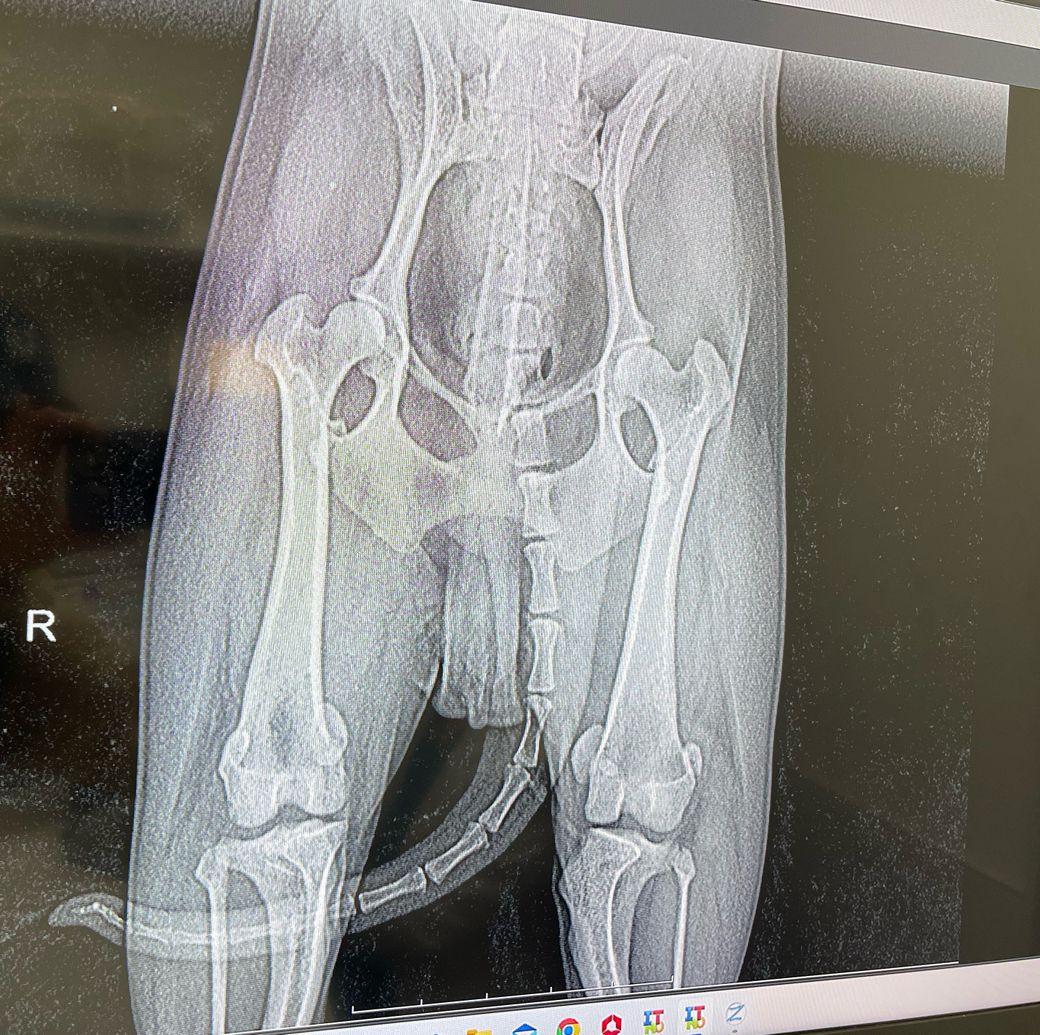

강아지 쓸개골 탈구 진단을 받았어요!

생각지도못한 쓸개골탈구 진단을 받았어요

사진보여드립니다~

1. 많이 심각한가요? 몇기정도 되나요?

3. 수술을 해야하는 상태인가요?

1. 슬개골탈구의 진단과 기수의 평가는 방사선 사진으로 하는게 아니라 손으로 만져보고 하는것이라 주치의의 의견을 준용합니다.

2. 아니요, 오히려 인대에 영향을 주어 십자인대 단열을 유발할 수 있습니다. 하지 마시기 바랍니다.

3. 슬개골 탈구는 구조의 질환이고, 구조의 질환은 수술만이 답이며, 예후는 수술을 빨리 하면 할 수록 좋다는게 정설입니다. https://diamed.tistory.com/357